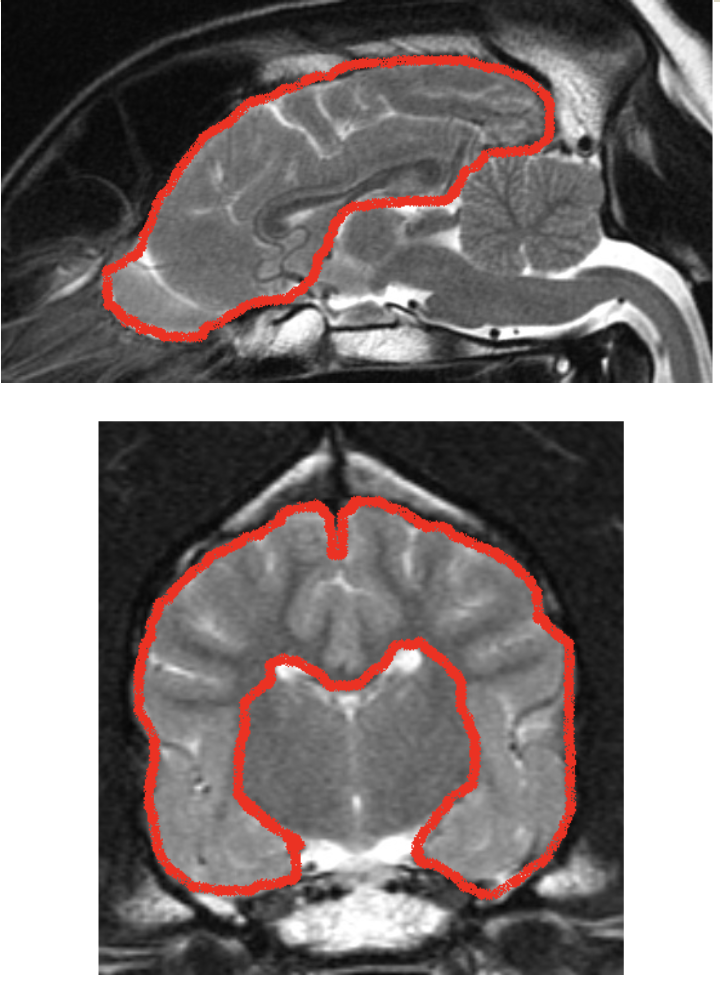

what is the cerebral hemisphere made up of

surface grey matter –> called cerebral cortex

underlying white matter and deep masses of grey matter –> called basal nuclei

each hemisphere contains a cavity –> lateral ventricle